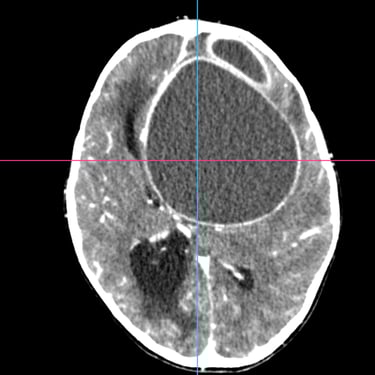

El absceso cerebral es una infección localizada del parénquima cerebral que produce acumulación de pus e inflamación, generando cefalea, fiebre, alteración del estado de conciencia o déficit neurológico focal. El diagnóstico temprano es fundamental para evitar complicaciones graves. La tomografía cerebral con contraste es el estudio de elección inicial, ya que permite visualizar una lesión hipodensa con realce en anillo característico. Posteriormente, la resonancia magnética complementa la evaluación. El tratamiento combina antibioticoterapia dirigida y, en casos seleccionados, drenaje quirúrgico o resección. La detección oportuna mediante imágenes mejora significativamente el pronóstico del paciente.